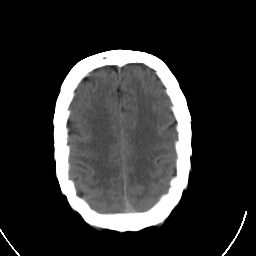

Stroke CT #3 -- Slice #19

[Home][Help][Clinical] Slice 19